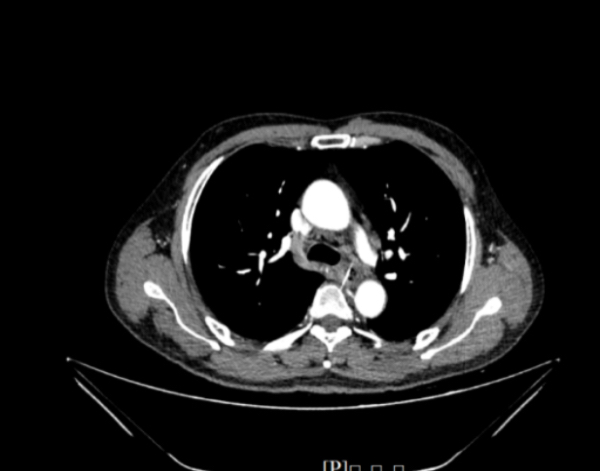

日前,患者彭先生晚餐时不慎被鱼刺卡住喉咙,随即出现胸口剧痛、呼吸困难。家人带其辗转多家医院,影像检查显示鱼刺位置极为凶险——已紧贴人体粗大的肺动脉,属于临床罕见的高危情况。因手术风险极高,稍有不慎可能导致动脉破裂,患者将出现生命危险,多家医院均表示难以处理。

生命垂危之际,彭先生被紧急转运至南方医院,消化内科接诊后立即启动应急预案,巩兰波教授、赵芯梅教授、韩泽民医生医疗组连夜集结,为患者进行全方位评估。精准影像显示,鱼刺与肺动脉之间仅有毫厘之隔,取出过程犹如“在万丈悬崖边行走”。